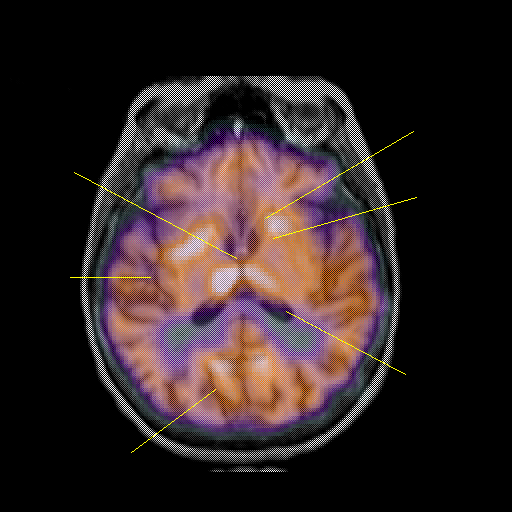

overlay: Slice 29

Slice 29

Pointers

Labeled